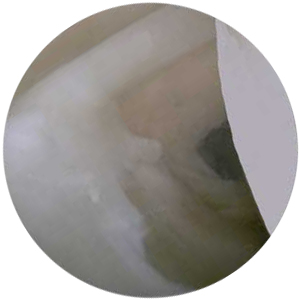

関節唇 カンセツシン を内視鏡で見た写真(イラストの黒のところが関節唇)

痛んでいる関節唇 カンセツシン ばさばさしているところとはがれているところ)

・その名の通り、関節唇の損傷です。関節唇とは、最初の写真の部分のことでボールを投げる瞬間に肩の中では負担がかかる場所です。